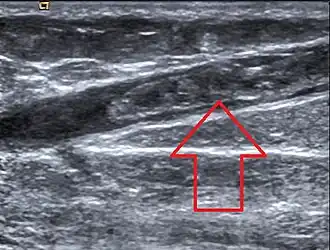

| Trombose da veia safena magna observada no exame de ultrassom | |